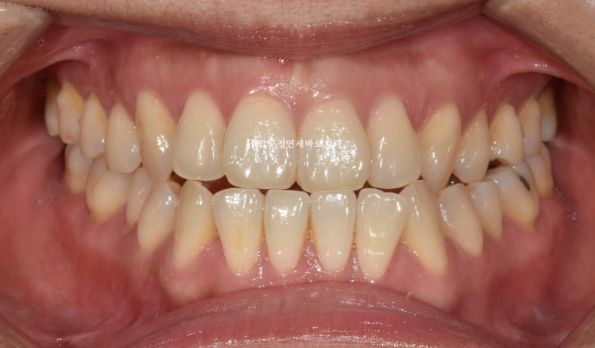

양악수술 교정을 위해 내원하신 분.

치아 중심선이 틀어져 있는 만큼 턱의 비대칭이 있고

23.01

어금니 뿐 아니라 앞니가 거꾸로 물리는 반대교합이므로 골격성 3급 부정교합으로 진단이 되었습니다.